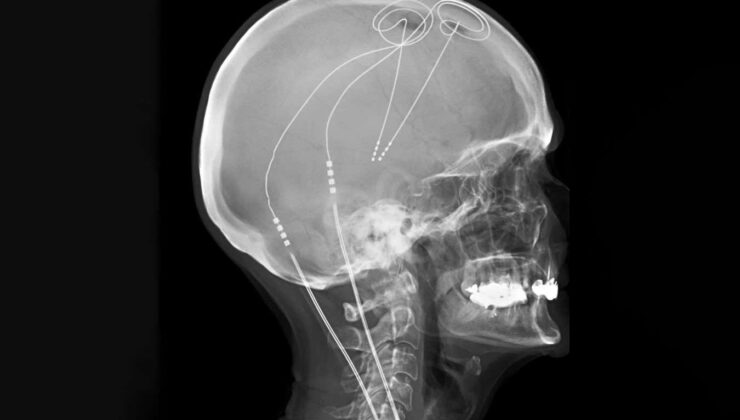

Yaşayan Sanat İşletmeleri/Bilim Fotoğraf Kütüphanesi

Derin beyin stimülasyonu (DBS), beyin Küçük elektrotlar kullanmak, umut vaat etti ancak tutarsız sonuçlara sahip. Geleneksel olarak, aynı beyin bölgeleri, ağrının farklı insanlarda farklı devrelerden kaynaklandığını gösteren kanıtlara rağmen, tek bedene uyan bir yaklaşımla hedeflenir.

Bu yüzden Prasad Shirvalkar Kaliforniya Üniversitesi, San Francisco ve meslektaşları kişiselleştirilmiş bir sistemin daha etkili olup olmayacağını merak ettiler. Öğrenmek için, daha önce tedavi edilemeyen kronik ağrıya sahip altı kişiye, elektrotların 10 gün boyunca beyinlerinde 14 bölgeden aktivite kaydettiği ve bunları uyardığı intrakraniyal elektroensefalografi uygulandı.

Araştırmacılar daha sonra makine öğrenimini kullandılar, bireyler yüksek veya düşük düzeyde ağrı yaşadığında meydana gelen elektriksel aktiviteyi tanımlamak ve ayırt ettiler. Daha sonra, beyin aktivitelerini izlemek ve ağrı ile ilgili aktivite tespit edildiğinde optimal stimülasyon sağlamak ve uyurken deaktive etmek için kişiselleştirilen her katılımcıya kalıcı DBS elektrotlarını implante ettiler.